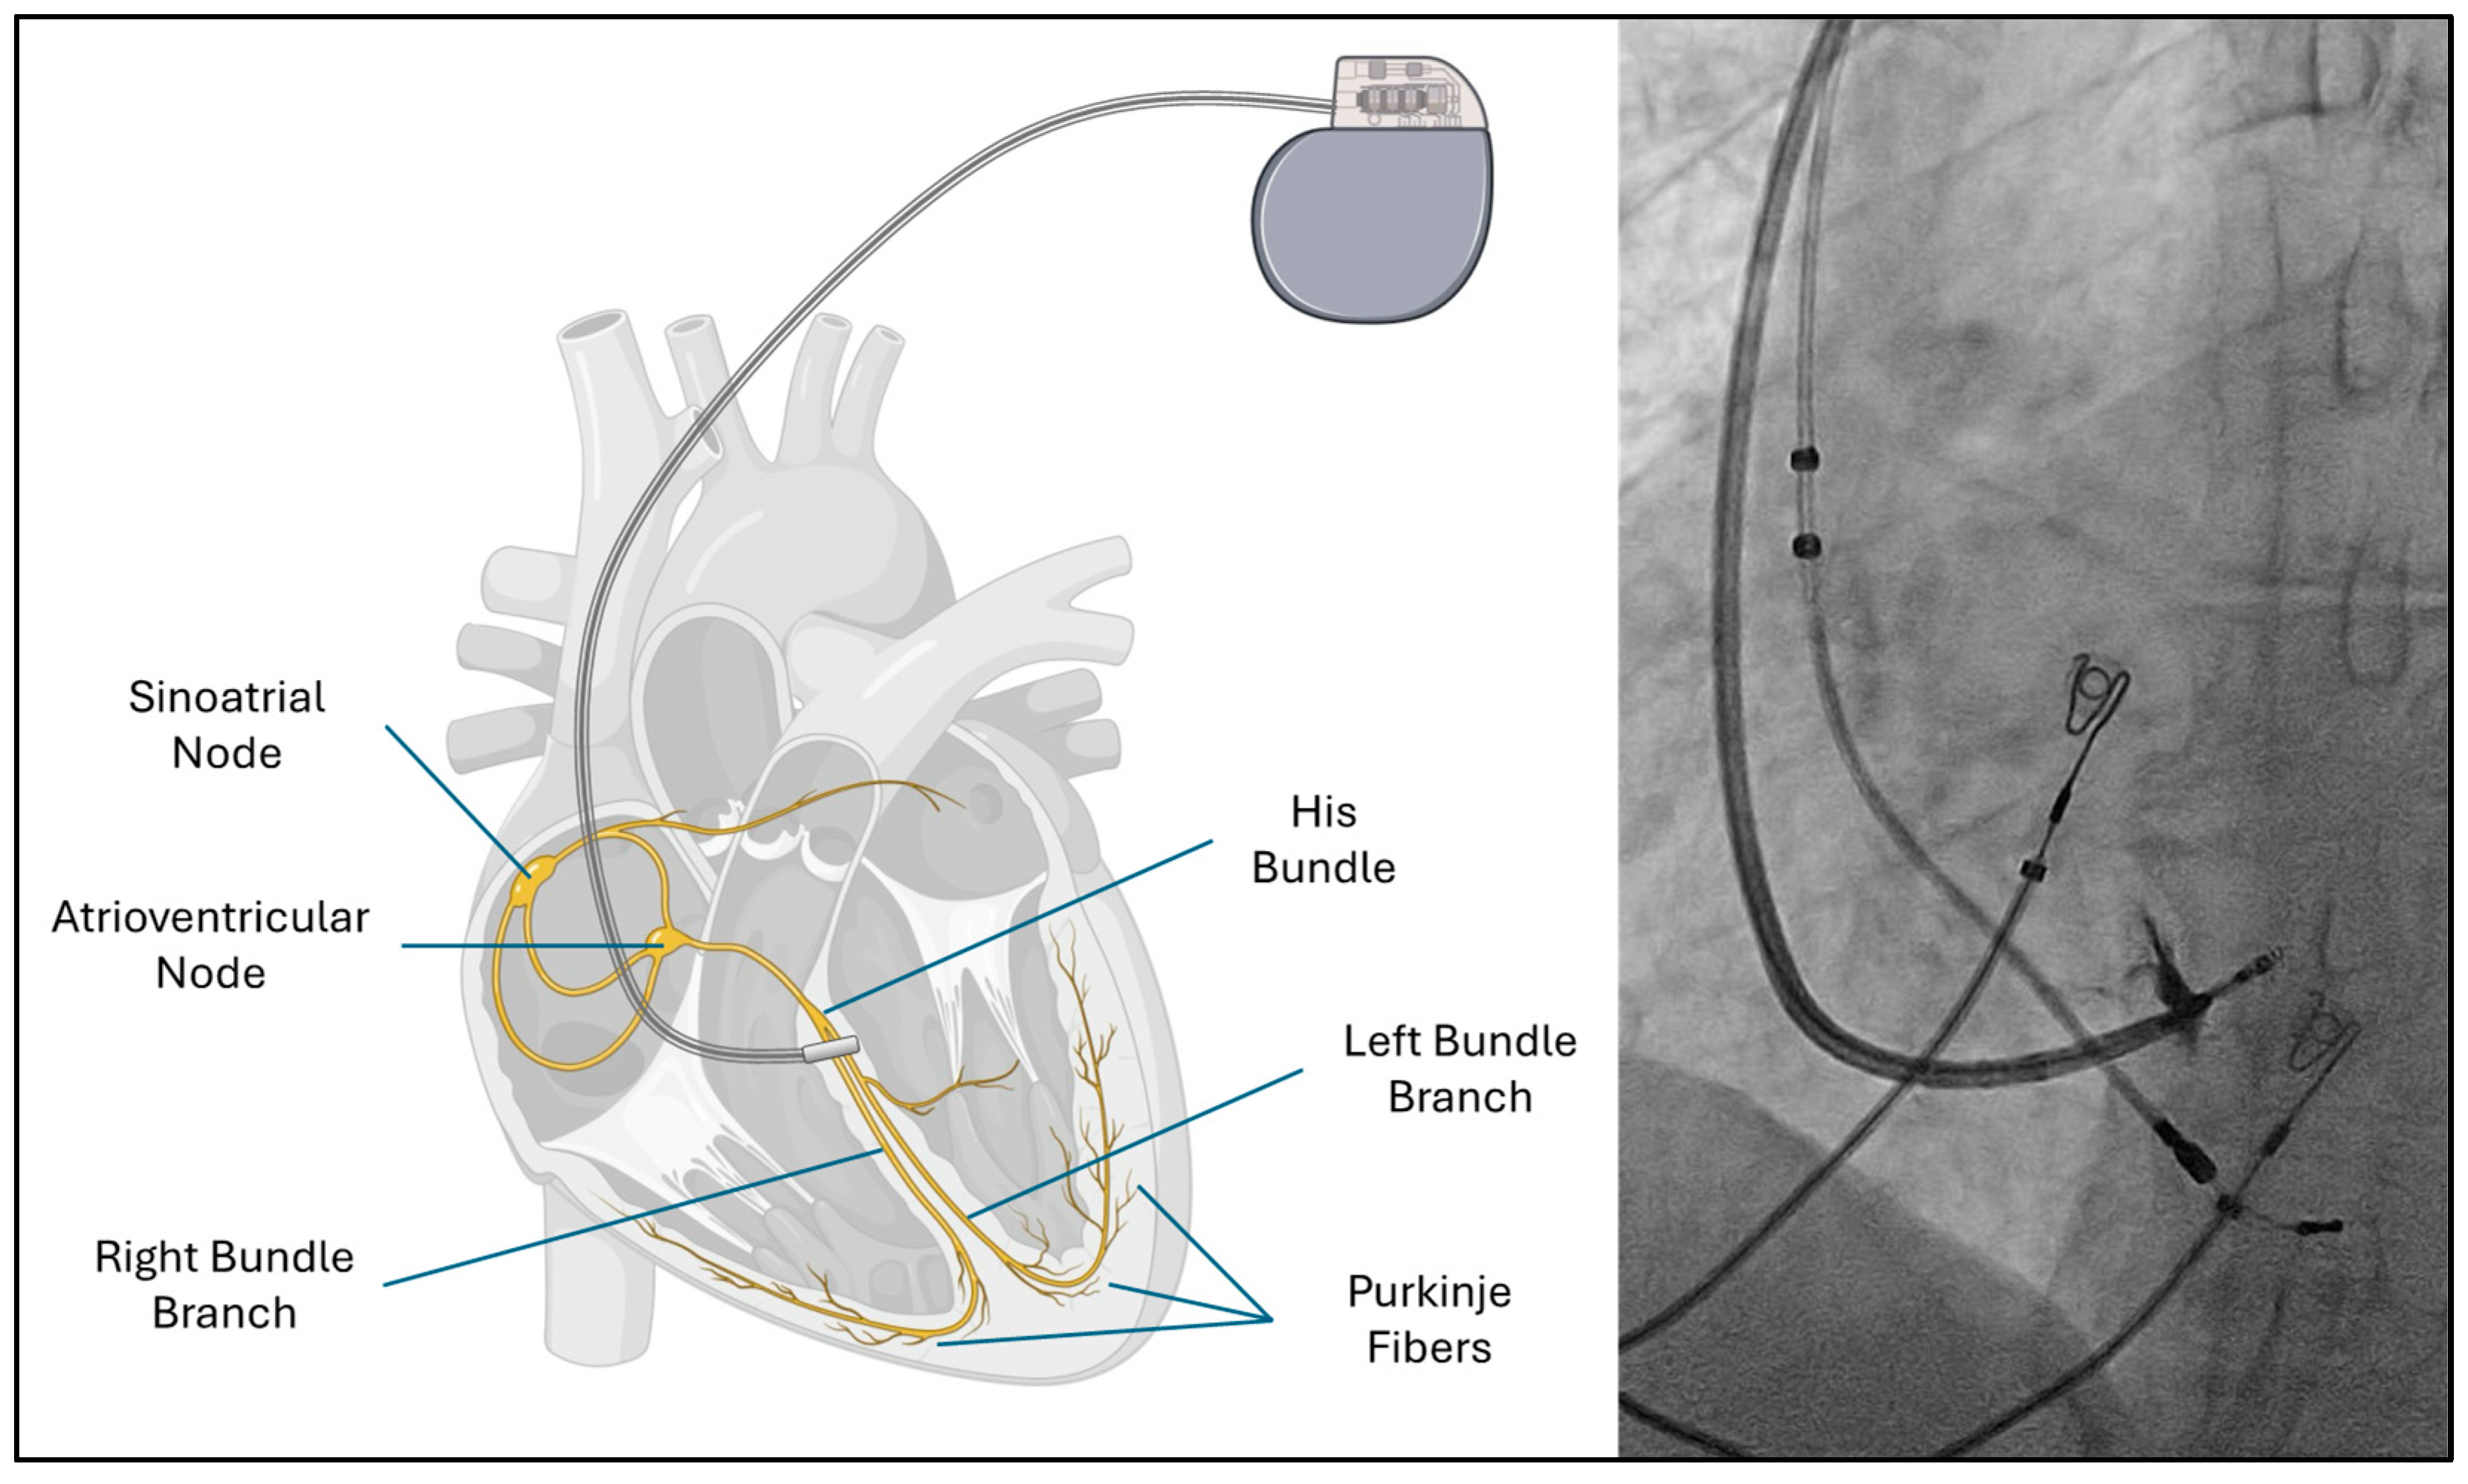

Bundle branch pacing (BBP) has emerged as a physiological alternative that directly engages the native conduction system through His bundle pacing or left bundle branch area pacing [6] (Figure 1). By restoring synchronized ventricular activation, BBP improves mechanical function and systemic hemodynamics. Early clinical evidence suggests this technique not only reduces dyssynchrony but also promotes reverse remodeling, decreases hospitalizations, and enhances the quality of life for patients with HFrEF [7].

Figure 1. A schematic diagram of the cardiac conduction system with placement of left bundle pacing lead (left). Fluoroscopic image (right).